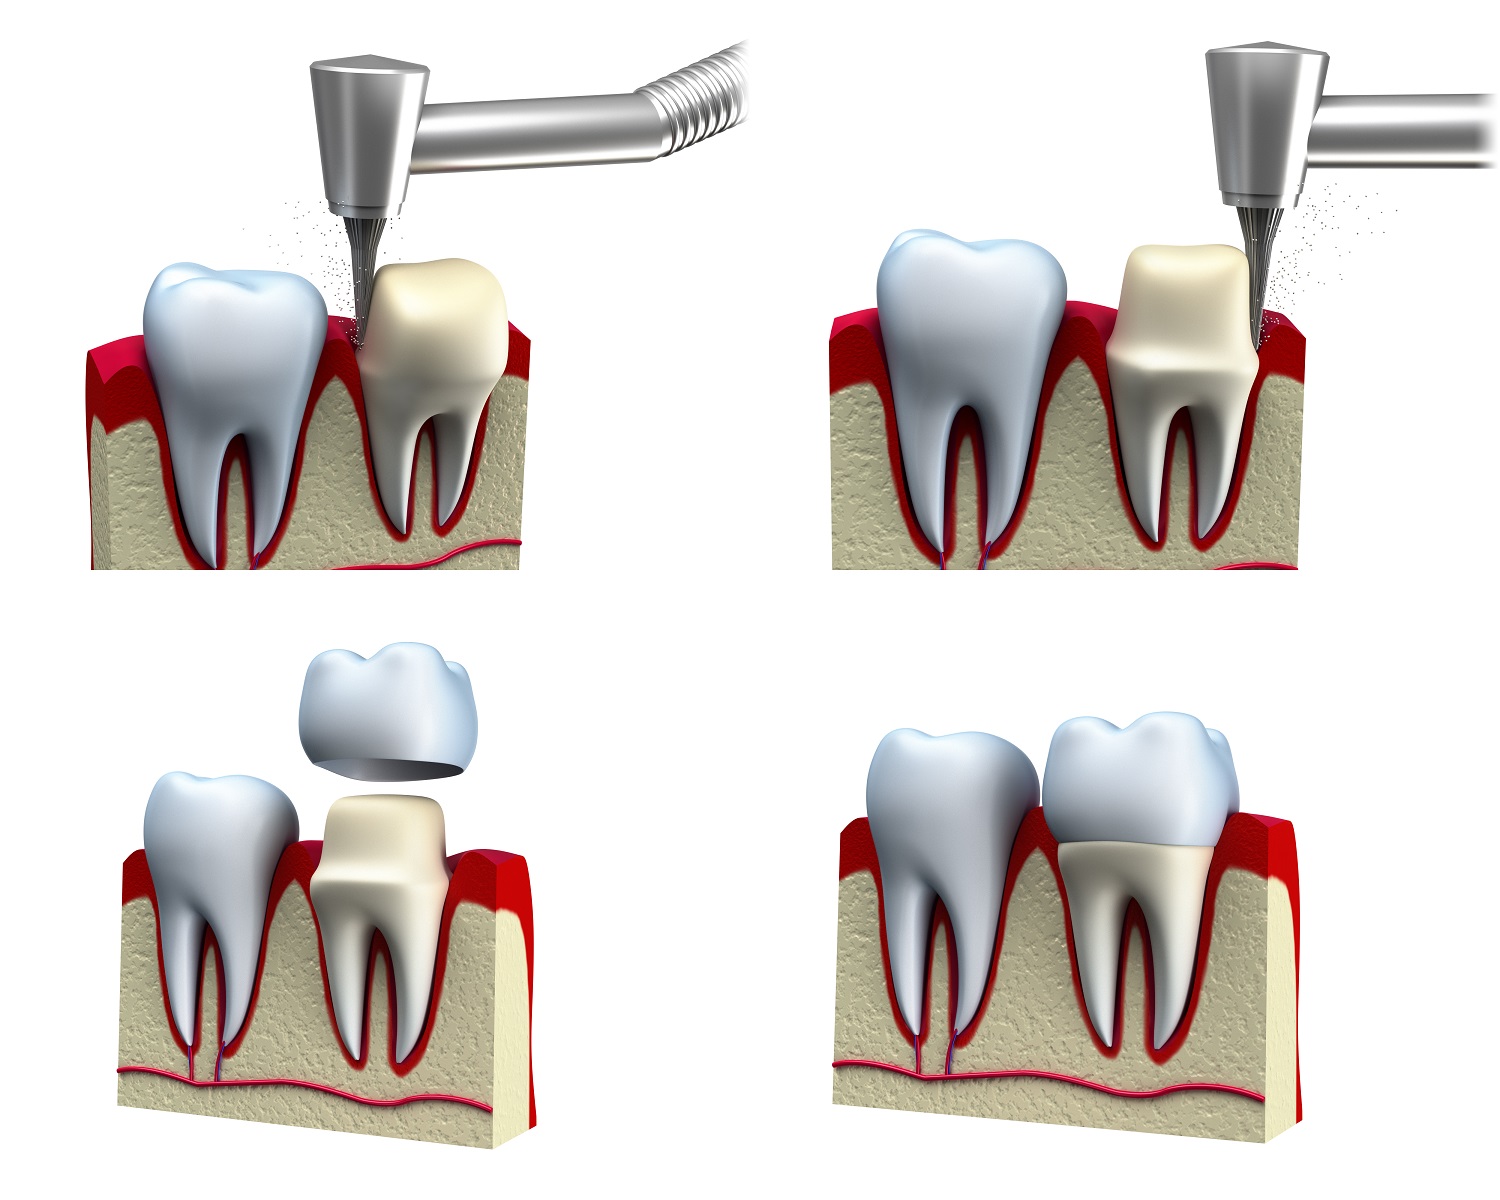

Porcelain Crowns

Understanding Porcelain Crowns

Porcelain crowns are one option used in dental care to cover and support teeth that have been structurally compromised. They are designed to cover the visible portion of a tooth and may be recommended in cases where a tooth has undergone root canal treatment, has extensive decay, or has been fractured.

The procedure generally involves two visits. At the first visit, the dentist prepares the tooth and takes an impression to assist in fabricating the crown. A temporary crown may be placed during this time. At the second visit, the custom-made crown is placed onto the tooth.

Porcelain crowns can help restore a tooth’s function and structure, and may help protect it from further wear. Your dentist will assess your individual needs and suitability for this treatment option.